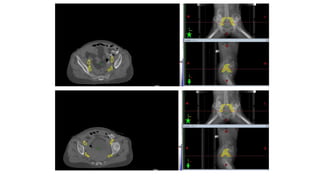

5. Contouring:

TARGET VOLUME….

1. Entire vulvar postoperative bed

2. Bilateral Inguino-femoral lymph node regions

3. Pelvic lymph nodes

1. VULVAR PRIMARY:

CTV tumour/ CTV 1>> Entire vulva

2. CTV NODAL:

1. Inguinal-femoral

2. Pelvic lymph nodes

(bilateral obturator and external and internal iliac)

INGUINOFEMORAL LYMPH NODES

First echelon lymphatic drainage>>

1. Superficial medial inguinal

2. Deep femoral lymph nodes.

• Anatomical compartment

• Laterally ----medial border of

the iliopsoas

• Medially ---- lateral border of

the adductor longus

• Posteriorly ----iliopsoas muscle

and pectineus

• Anteriorly ---edge of the

sartorius muscle and

rectus femoris

(Kim et al. 2012)